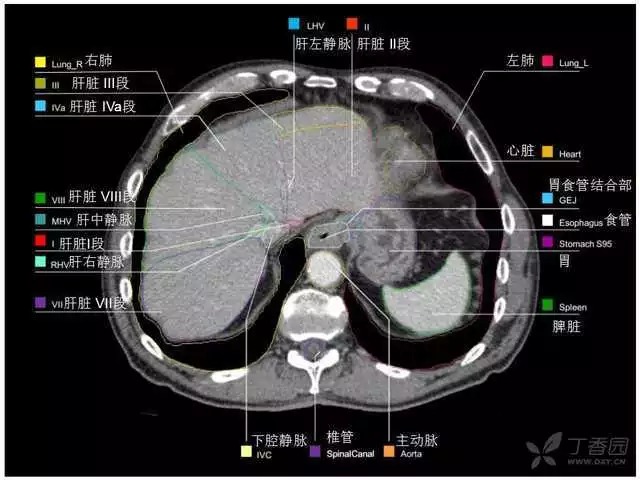

腹部肝脏高清CT断层的图谱

全腹部高清CT图谱,淋巴结彩色图谱,血管解剖图谱大汇总!

肝段,肝内管道的分布规律

美国放射学会ACR官网,对肝脏的区域和节段解剖学概述